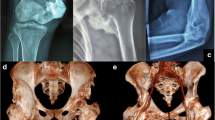

Research shows the prevalent presence of TGF-β signaling pathways within sensory nerves [197] and in astrocytes, it not only enhances protein expression but also modulates its own signaling pathway [198, 199]. Systemic injection of a TGF-β neutralizing antibody attenuates HO in BMP-induced spontaneous HO models in mice [24]. With intact BMP receptors, MSCs serve as BMP target cells in bone, with BMP being an effective inducer of osteoblast differentiation in vitro [22]. The TGF-β signaling pathway in astrocytes can inhibit inflammation and alleviate neuronal injury within the central nervous system [200] (Fig. 1).

Role of neuromodulation in HO after nerve injury. Blood levels of BMPs and TGF-β rise in response to damage to brain or nerve fibers, and these molecules directly influence intracellular signaling pathways to contribute to HO. Mast cells, macrophages and astrocytes are activated and accompanied by the release of neurotrophic factors following nerve injury. These neurotrophic factors in conjunction with BMPs and TGF-β combine with its corresponding receptor respectively and activate the signaling pathways to promote the progression of HO